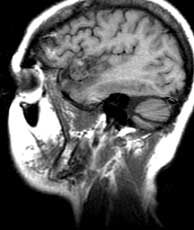

T1 sagittals pre-gad

Findings:

Mixed signal mass (a) in the left Sylvian fissure with surrounding low signal encephalomalacia.